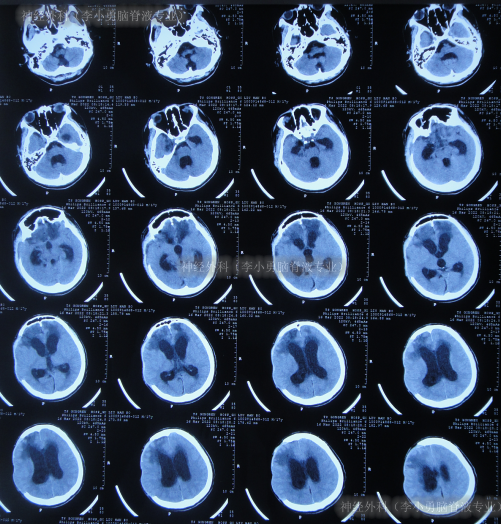

因脑积水进一步加重,于2022年3月28日(去骨瓣减压术后55天),进行了脑室腹腔分流术。术后次日查头颅CT示脑室分流术后有出血(图-8)。

图-8:2022年3月29日头颅CT

脑室腹腔分流术后4天即2022年4月1日,查头颅CT示脑室明显缩小(图-9)。

图-9:2022年4月1日头颅CT

脑室腹腔分流术后8天即2022年4月5日,查头颅CT示脑室周仍有水肿(图-10)。

图-10:2022年4月5日头颅CT

脑室腹腔分流术后31天即2022年4月28日,查头颅CT示脑室又变大(图-11)。

图-11:2022年4月28日头颅CT